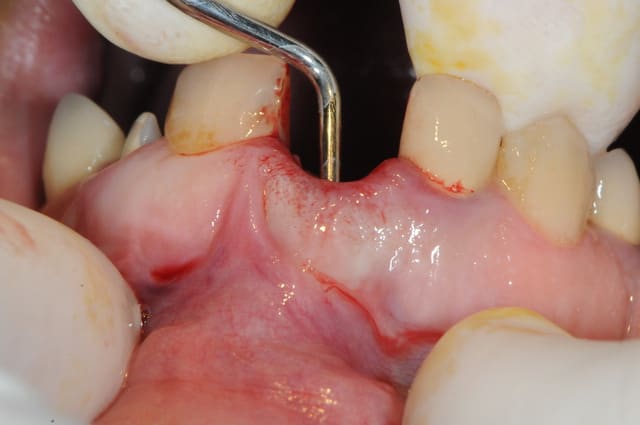

un cas où j'ai préféré extraire , implanter, combler et temporiser avec un petit bridge provisoire selfmade collé.

c'est quoi les deux points de suture vest ?

Pour répondre à Rhizalye je crois pourvoir dire que ce sont des points en U.

Toutefois Growler ce qui m'intéresse sur ton cas ce serai de connaitre le comportement de ton comblement; il semble pouvoir s'exposer à 8 jours, non?

+1 . Quel materiaux de comblement as tu utilisé ?